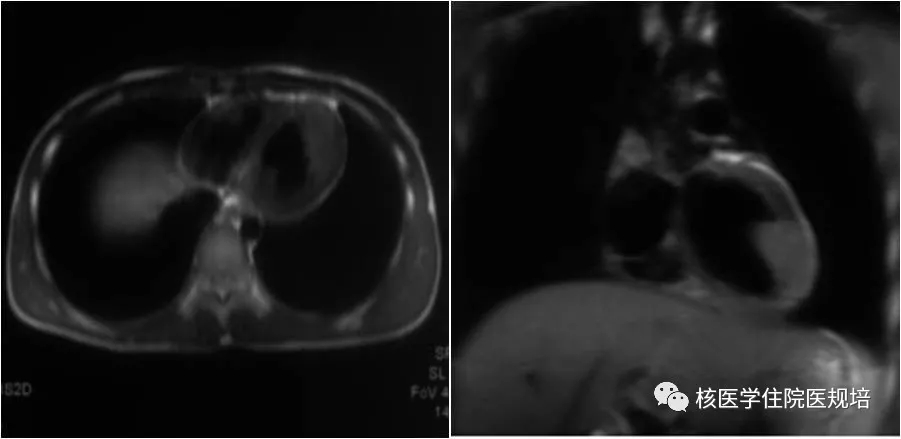

患者男性,20岁,2月前因发热待查就诊,影像学检查发现心脏占位。心脏超声示:左室前侧壁占位,彩色多普勒血流成像可见肿物血供丰富(图1);心脏MR示:左室中段及心尖段前侧壁占位,累及前组乳头肌,前侧壁可见粗大肿瘤血管(图2)。为明确左心室病变性质,行18F-FDG PET/CT显像(图3)。

图1

图2